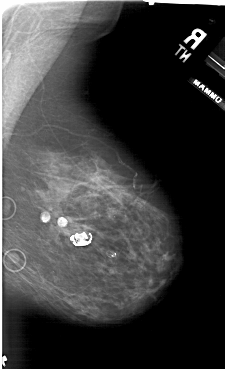

A_1941_1.LEFT_MLO

LEFT_MLO LINES 5986 PIXELS_PER_LINE 4276 BITS_PER_PIXEL 12 RESOLUTION 43.5 OVERLAY

FILE: A_1941_1.LEFT_MLO.OVERLAY

TOTAL_ABNORMALITIES 1

ABNORMALITY 1

LESION_TYPE CALCIFICATION TYPE PLEOMORPHIC DISTRIBUTION CLUSTERED

ASSESSMENT 4

SUBTLETY 2

PATHOLOGY BENIGN

TOTAL_OUTLINES 1

BOUNDARY